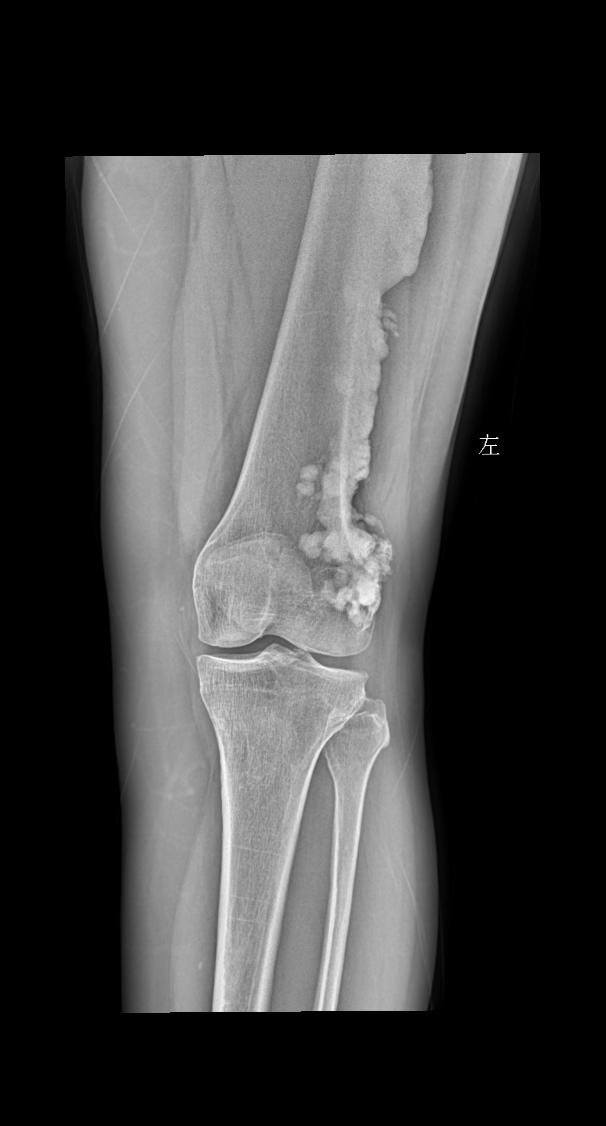

女 55 左侧关节疼痛

2025-09-11 18:45